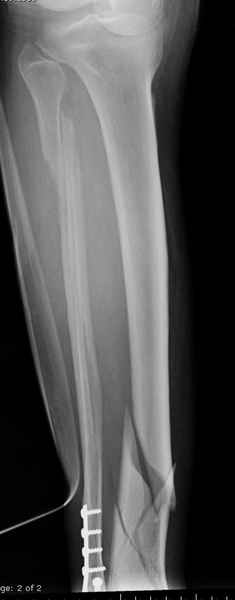

спрашивает что делать с больным который поступил недавно, фермер 55 лет падение при пьяной драке в баре, года два назад перенес операцию на лодыжке, на снимках и КТ перелом без вовлечения сустава,

Повреждение такой локализации, на которой применимы и аппарат (классический Илизарова или гибридный), пластина, особенно Locked Plate, и гвоздь с блокированием. В нашей клинике был бы выполнен закрытый интрамедуллярный остеосинтез. Желательно использовать гвоздь с возможностью провести более чем 2 обычных фронтальных винта в дистальном отломке.

Здесь мы использовали новый Synthes Nail с дополнительными дырками, в проксимальной части 4: по две косых и поперечные (один стандартный а другой динамический), в дистальной части две поперечные, прямая и косая. Вес больного более 120 кг, нагрузку начнем через месяц.

При такий спирали задний край tibia может быть сломан - нет ли этого в данном случае? На всякий случай можно было ввести 1-2 винта 4,5 мм спереди назад мимо гвоздя. Хотя самый дистальный блокирующий винт, возможно, зацепил этот отломок. А какой тут диаметр гвоздя и locking винтов?